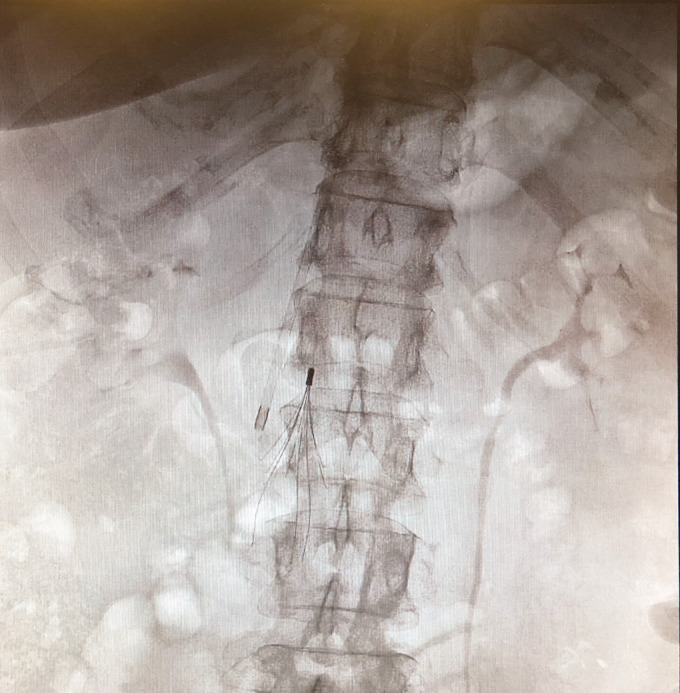

股总静脉浮静脉血栓具有肺动脉栓塞的高潜在风险。临床治疗,使用抗凝剂或纤溶剂,开放血栓切除术,或血管内装置血栓切除术都已被使用。我们的病例描述了一名肥胖患者,他受到来自GSV的漂浮血栓的影响,并潜入股总静脉,通过联合临时腔静脉插入和开放手术取栓成功治疗。

The floating venous thrombus in the common femoral vein has a high potential risk for pulmonary embolization. Clinical treatments, using anticoagulants or fibrinolytic, open thrombectomies, or thrombectomies by endovascular devices have all been used. Our case describe an obese patient affected by floating thrombus coming from GSV and diving in common femoral vein successful treated by combined both temporary vena cava insertion and open surgical thrombectomy.